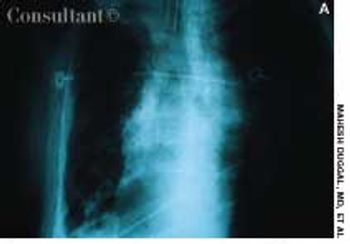

The pattern of pleural calcification and the patient's history are helpful in determining the usually remote cause of the calcification. Here, Drs Mahesh Duggal, Achal Dhupa, Krishna Badhey, and Arunabh of North Shore University Hospital of Forest Hills, NY, offer 2 cases that illustrate the importance of these data.